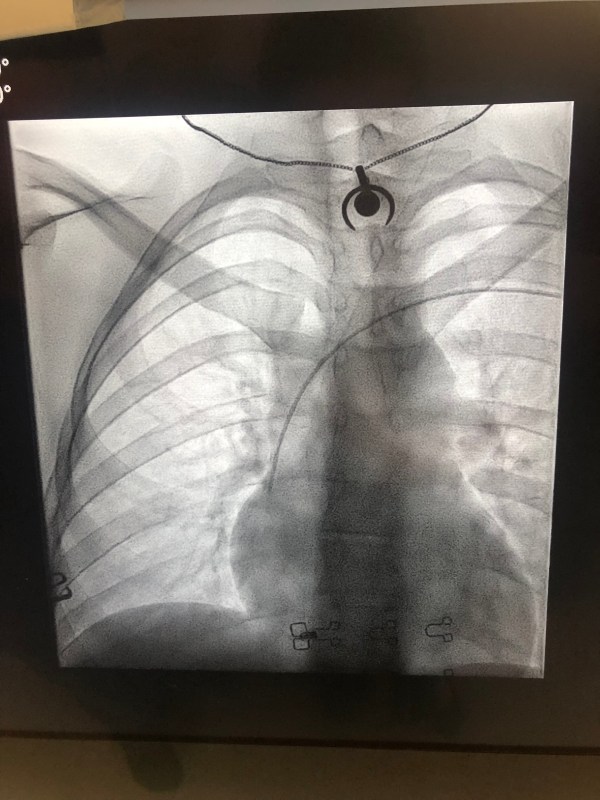

PICC Lines 101: What, Why, How…Ow?

I've been meaning to do a write up about my PICC line for the last week, but time got away from me a bit as I also started chemotherapy. So, apologies about the delay as this is one of the topics I've received the most questions about!